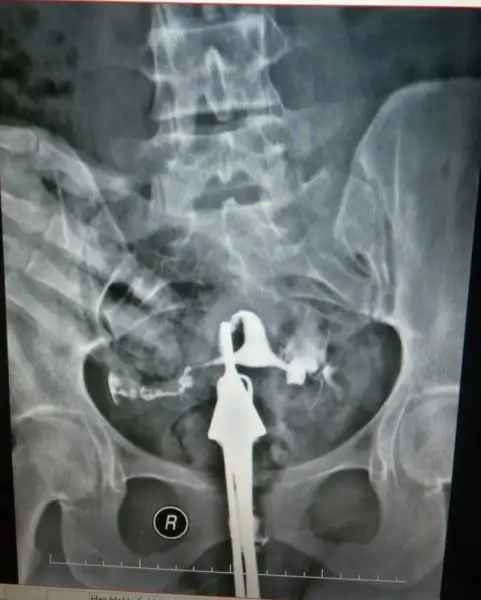

Ay herkesin rahmi ne kadar da farklı neresi neresi çözmek için 5 dakika baktım resme evire çevire. tüplerin açık onu anladım ama rahim arkaya doğru yatmış ya galiba , yapışıklık vs var mı yok mu hiç anlamadımKızlar yükledim sonunda yorumlarmısınız

Aynen bende oyle dusundum Rabbim farklı farklı yaratmışAy herkesin rahmi ne kadar da farklı neresi neresi çözmek için 5 dakika baktım resme evire çevire. tüplerin açık onu anladım ama rahim arkaya doğru yatmış ya galiba , yapışıklık vs var mı yok mu hiç anlamadım

Bak cnm rahmin şekilleri yandan bakılınca ilk resim normal olanı seninki bence 3. Resme benziyor retroflexed rahimAynen bende oyle dusundum Rabbim farklı farklı yaratmış

Ben dra sordum bariz ters duran rahim normalmiş hsg cektirdiğimde de normal demişlerdi ben anlamadım neye gore twrs neye gore duz

Sen yine anliyosun ben hic anlamiyorum rahim hangisi tupler neresi acik olduğunu nere anliyosunuz hiç bilmiyorum nasil arkaya yatmış kiAy herkesin rahmi ne kadar da farklı neresi neresi çözmek için 5 dakika baktım resme evire çevire. tüplerin açık onu anladım ama rahim arkaya doğru yatmış ya galiba , yapışıklık vs var mı yok mu hiç anlamadım